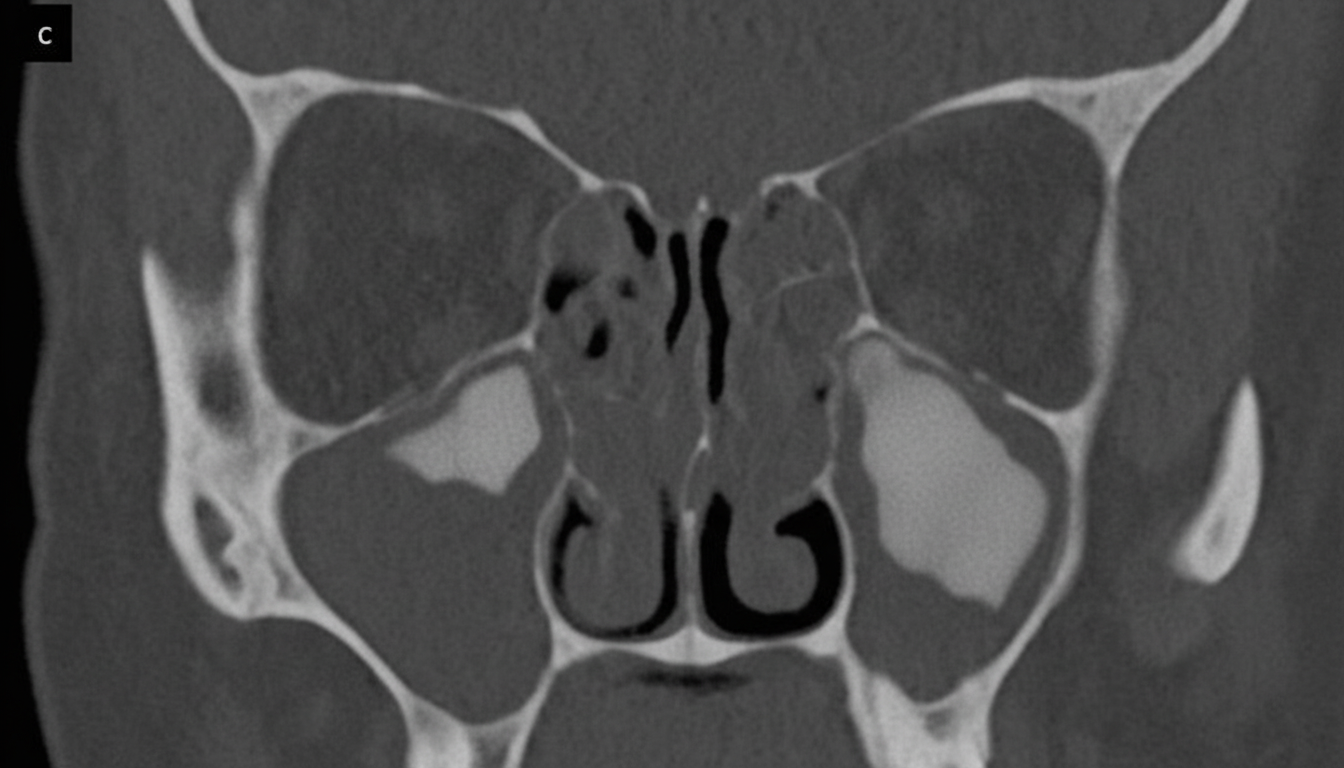

Explanation: ***Antrochoanal polyp*** - CT scan typically shows a **smooth, soft tissue mass** originating from the **maxillary sinus** extending through the **accessory ostium** with a characteristic **dumbbell appearance** into the choana and nasopharynx. - Common in **adolescent females** presenting with **unilateral nasal obstruction**, which matches this clinical presentation perfectly. *Juvenile Nasopharyngeal Angiofibroma* - This condition occurs **exclusively in adolescent males** due to hormonal influences, making it impossible in a 16-year-old girl. - CT shows a **highly vascular mass** in the nasopharynx with **epistaxis** as a prominent symptom, which is not mentioned here. *Nasopharyngeal carcinoma* - Typically occurs in **older adults** (40-60 years) and is rare in adolescents, especially without associated symptoms like **hearing loss** or **cranial nerve palsies**. - CT shows **irregular, infiltrative masses** with **cervical lymphadenopathy**, unlike the smooth appearance of antrochoanal polyps. *Adenoid hypertrophy* - More common in **younger children** (3-7 years) and typically causes **bilateral nasal obstruction** rather than unilateral symptoms. - CT shows **symmetric enlargement** of adenoid tissue in the nasopharynx without the characteristic **maxillary sinus origin** seen in antrochoanal polyps.

Explanation: **Explanation:** The correct answer is **B. Maxillary sinus**. The clinical scenario describes a nasal polyp causing airway obstruction. In clinical practice, the most common type of nasal polyp is the **Antrochoanal polyp**. These polyps originate from the mucosa of the **maxillary sinus** (specifically near the accessory ostium). They grow to fill the maxillary antrum, exit through the natural or accessory ostium into the middle meatus, and then extend posteriorly toward the choana, obstructing the airway. Because the polyp physically occupies the ostium of the maxillary sinus as it exits, it directly leads to the obstruction of drainage from that specific sinus. **Analysis of Incorrect Options:** * **A. Sphenoid sinus:** This sinus drains into the sphenoethmoidal recess, located far posterior and superior to the typical path of an antrochoanal or ethmoidal polyp. * **C. Ethmoidal sinus:** While ethmoidal polyps (multiple/bilateral) originate here, the question implies a single obstructing mass. Even in ethmoidal polyposis, the primary drainage of the maxillary sinus (via the middle meatus) is more frequently compromised by the bulk of the polypoid tissue. * **D. Frontal sinus:** This drains into the frontal recess of the middle meatus. While it can be obstructed by large polyps, the maxillary sinus is the primary site of origin for the classic solitary obstructing polyp (Antrochoanal). **NEET-PG High-Yield Pearls:** * **Antrochoanal Polyp (Killian’s Polyp):** Usually solitary, unilateral, and seen in children/young adults. It has three parts: Antral, Nasal, and Choanal. * **Radiology:** On CT, it appears as a soft tissue mass filling the maxillary sinus and extending into the nasopharynx through the widened ostium (**"Dumbbell shape"**). * **Treatment of Choice:** Functional Endoscopic Sinus Surgery (FESS). Simple polypectomy has a high recurrence rate.